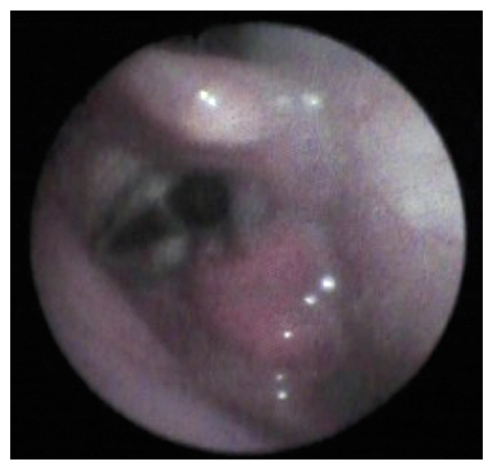

Визуализационная картина фиброоптического эндоскопического исследования с целью определения степени дисфагии отражена на рис. 5, 6.

Рис. 6. Неполное смыкание голосовой щели, парез левой голосовой связки соответствуют тяжёлой степени дисфагии (4 балла по шкале PAS, 4 балла по шкале FEDSS).